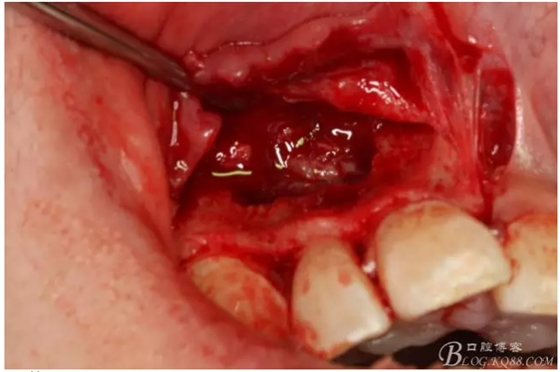

圖2.根管治療術后直接局部 麻醉下切開、翻瓣,發(fā)現(xiàn)12唇側骨壁有綠豆大小骨缺損

圖3.依缺損部位為中心,逐漸去骨,完整暴露出囊壁。